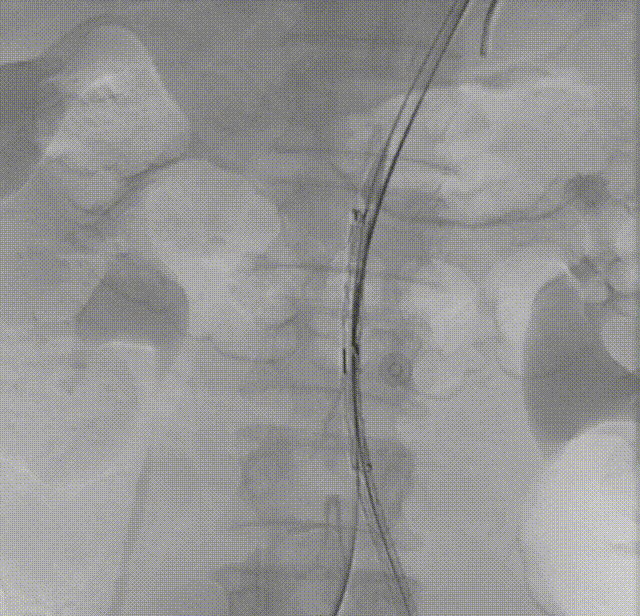

2. 经左侧股动脉入路,建立至降主动脉的输送通道,交换导丝,送入MOB球囊,将球囊位置推送至肾动脉以下,充盈球囊,阻断血流。

4. 穿刺左桡动脉,经左锁骨下动脉通过,输送导丝及椎管,输送至球囊近端附近,造影确认肾动脉位置。

gore医疗怎么样「漫腹精论」髂合时宜 精益求精——双MOB球囊导管辅助腹主动脉覆膜支架急诊治疗破裂巨大髂动脉瘤_https://www.jmylbn.com_新闻资讯_第15张